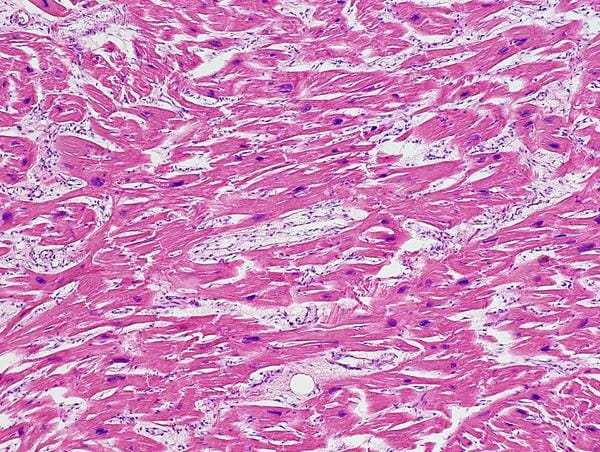

Obraz mikroskopowy mięśnia sercowego z uwidocznionym przerostem.

Ryc. C – prawidłowy obraz histologiczny mięśnia sercowego. Ryc. D – preparat histopatologiczny serca, które uległo hipertrofii. Między włóknami tkanki mięśniowej znajduje się nagromadzenie tkanki włóknistej, której obecność w tym miejscu świadczy o procesie zwyrodnieniowym.

Adaptacja jest procesem pozwalającym na przezwyciężenie problemów. Niestety, gdy czynnik uszkadzający trwa zbyt długo nie dochodzi do uzyskania pozytywnych efektów. Dodatkowo, gdy stresor jest silny może dojść do szybko postępujących zmian zwyrodnieniowych wewnątrz włókien w tym do ich fragmentacji i utraty elementów kurczliwych. Serce niekurczące się nie daję możliwości cieszenia się z życia.